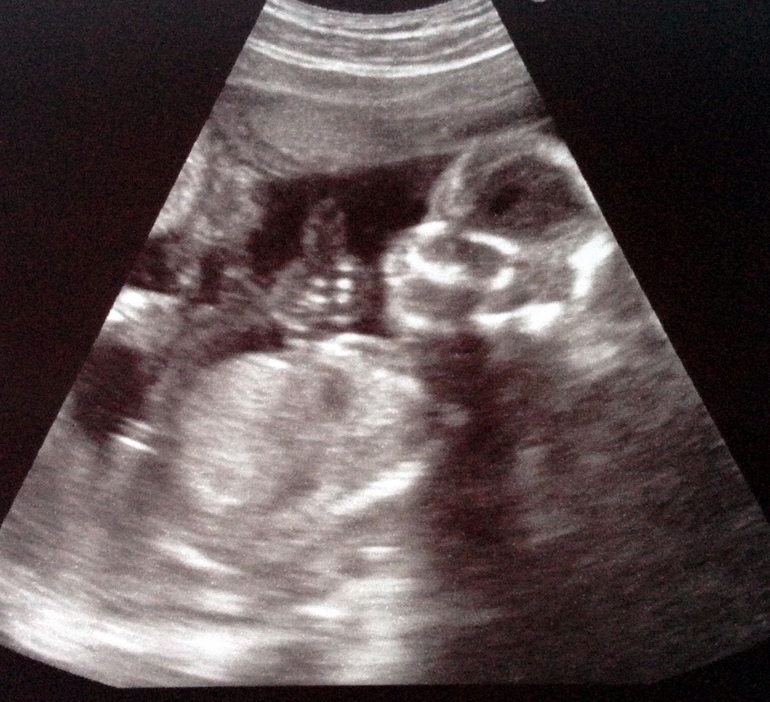

Пол малышаБыла вчера на УЗИ. 16 недель 6 дней.

Все хорошо, ребенок опережает пока в развитии на 3 дня.

Т.к. я не была на первом скрининге, посмотрели носовую косточку, сказали норма. Все показатели в норме для этого срока. Весит 198 грамм.

Сидит на попе.

Нам фотки распечатали, думала качество получше будет.

Девочки можете мне стрелочками указать где что? Я вижу только голову. И то не пойму где там нос.